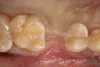

In the case presented, a 56-year-old male patient had a coronal fracture on tooth No. 13, which was deemed hopeless (Figure 1). Treatment options were discussed with the patient, including endodontic therapy followed by surgical crown lengthening with forced tooth eruption to expose sound tooth structure for prosthetic tooth reconstruction. Due to the short length of the residual root, however, an unfavorable prognosis was assigned to this treatment option. The clinician determined, therefore, that replacement of the tooth with a dental implant would be the most conservative, viable, and predictable option for tooth replacement since significant tooth reduction of unrestored adjacent teeth would be necessary for three-unit fixed-bridge fabrication and the patient did not accept any removable replacement options.

Fig 1. Hopeless maxillary second premolar.

Figure 1